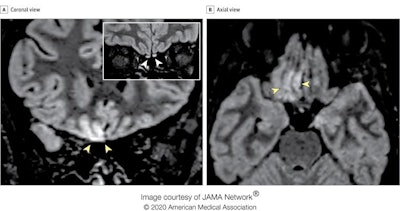

Brain MRI alterations in radiographer with COVID-19 who presenting with anosmia four days from symptom onset. Coronal (A) and axial (B) reformatted 3D fluid-attenuated inversion recovery (FLAIR) images show cortical hyperintensity in the right gyrus rectus (yellow arrowheads in A and B). In the inset in A, a coronal 2D FLAIR image shows subtle hyperintensity in the bilateral olfactory bulbs (white arrowheads). The cortical hyperintensity is present only in the posterior portion of the right gyrus rectus (B). Accordingly, the cortical hyperintensity of the right gyrus rectus is evident in the more posterior coronal image (A) and not in the anterior coronal one (inset). All images courtesy of JAMA Network.The researchers performed two MRI exams on a 1.5-tesla scanner using a 20-channel phased-array head/neck coil. They used no contrast agent and acquired 2D and 3D FLAIR, T2-weighted turbo spin-echo, T1-weighted spin-echo, and high-resolution diffusion-weighted images, Constructive interference in steady-state and susceptibility-weighted imaging sequences were employed.